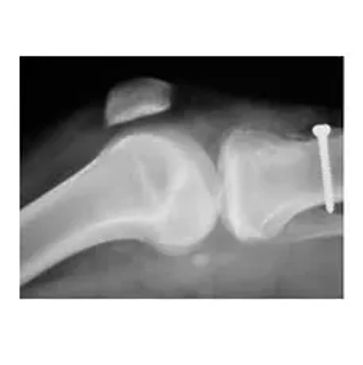

Bioretec has developed biomaterial based self-disintegrating bone nails and screws to repair bone fractures. Recently, an antibiotic screw was also granted marketing authorization. https://bioretec.com/